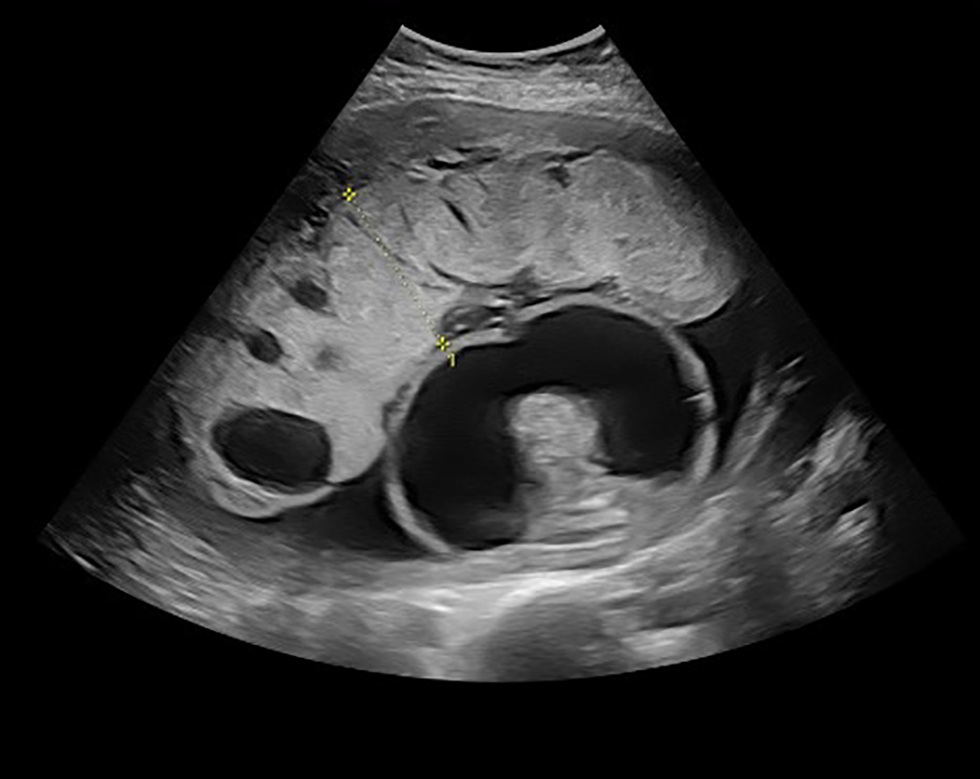

| Culture virale | Liquide amniotique | Négatif |

Le traitement se poursuit au moyen de la pénicilline par voie intraveineuse dans l'espoir d'atteindre des niveaux suffisants pour traiter l'infection fœtale. Après neuf jours, une échographie détaillée répétée a démontré une aggravation de l'ascite fœtale. Le fœtus avait maintenant un âge gestationnel de 20+5 semaines avec une circonférence abdominale de 282 mm (taille à 32+2 semaines) (figure 4). L'œdème du cuir chevelu et les résultats de l'échographie Doppler sont demeurés stables. La famille a reçu des conseils détaillés sur les options, y compris l'interruption de grossesse ou la gestion de grossesse à l'aide d'une série d'échographies et d'imageries par résonance magnétique fœtale pour suivre les changements neurologiques structuraux. Dans l'ensemble, le pronostic était jugé médiocre compte tenu de l'étendue de l'hydrops fetalis au début de la gestation et de la gravité des changements dans le cortex cérébral. Ultimement, la famille a décidé de mettre fin à la grossesse. L'induction médicale du travail a été effectuée avec la mifépristone suivie du misoprostol par voie vaginale. Un nourrisson hydropique mort-né de sexe féminin a été mis au monde révélant une mort intrapartum, à un âge gestationnel de 21+0 semaines et pesant 747 g (plus du 99e centile pour l'âge gestationnel). La famille a refusé une autopsie. Le placenta pesait 387 g (plus de deux fois le poids moyen pour cet âge gestationnel) avec des signes pathologiques d'hémorragie déciduale, de nécrose et d'inflammation aiguë.

Figure 4 : Aggravation des ascites avec un abdomen ayant la taille de celui d'un fœtus ayant un âge gestationnel de 32 semaines à un âge gestationnel de 20+5 semaines

Description textuelle : Figure 4

Image par échographie, prise à l'âge gestationnel de 20+5 semaines. Le fœtus est vu de profil, avec un abdomen très distendu et des ascites graves évidentes. Ce jour‑là, l'abdomen fœtal est mesuré comme ayant la taille d'un fœtus d'environ 32 semaines.